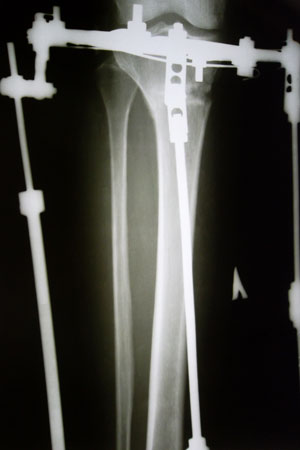

Рентген в 2 месяца с момента операции.

Вложения

SAM_8978.JPG

SAM_8980.JPG